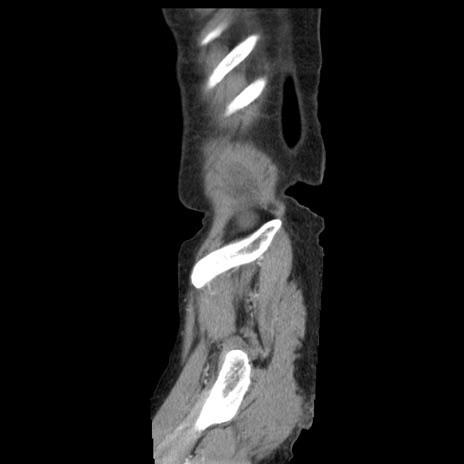

横断像